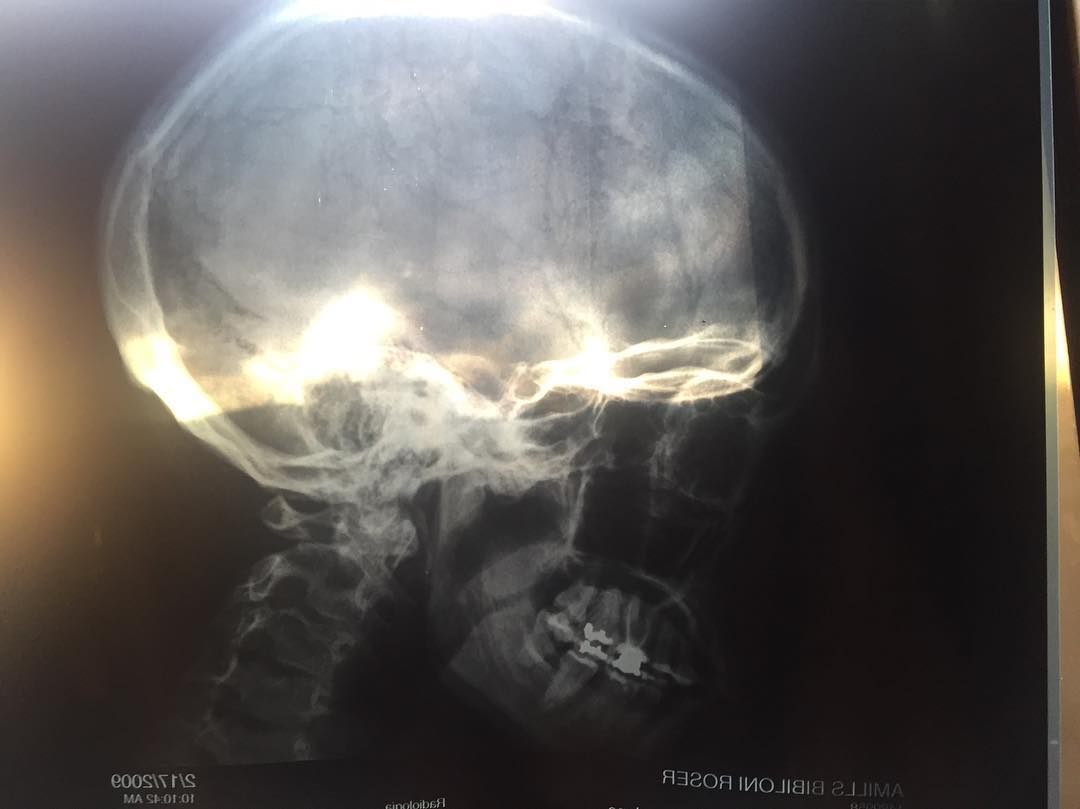

Mi cabeza, por dentro: la «cajita de cal».Y el mercurio que ya no tengo desde hace años